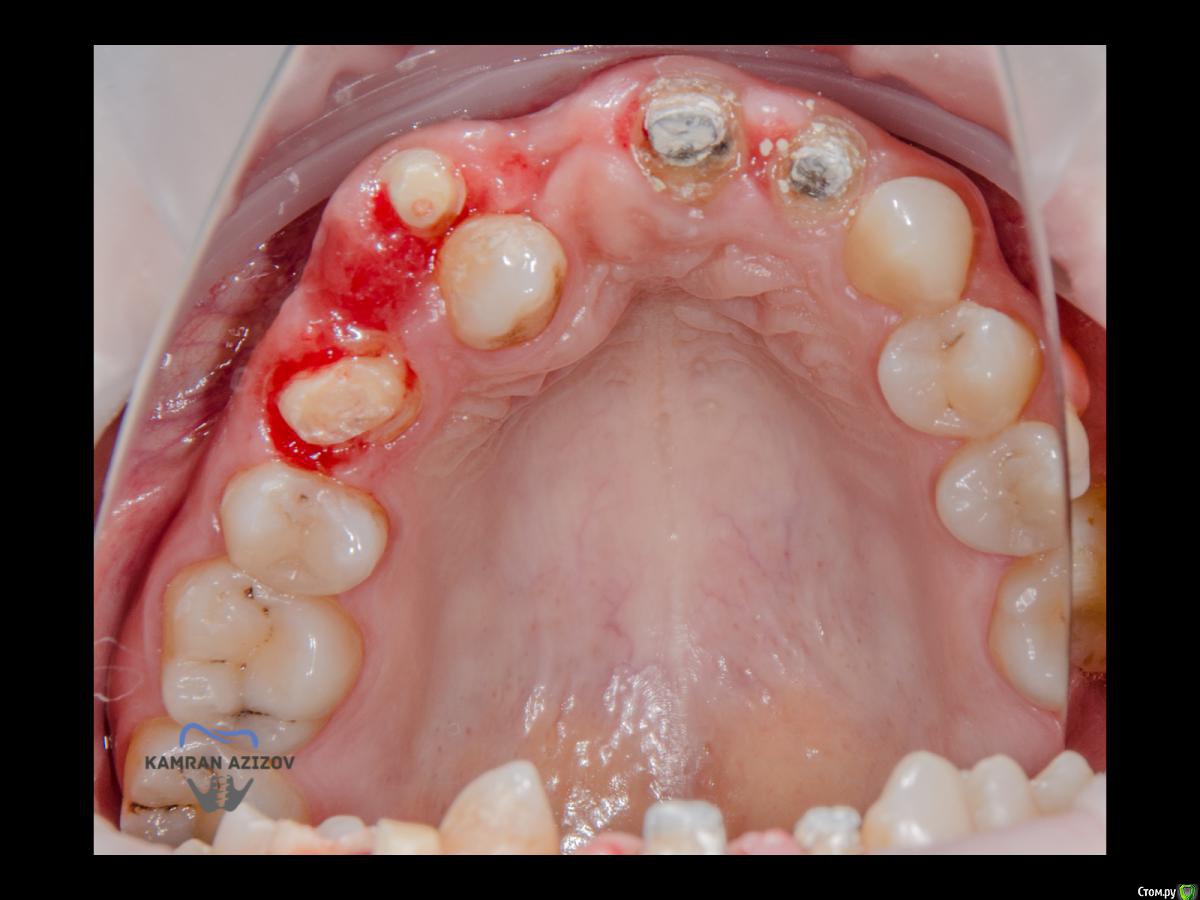

kamranchick Опубликовано 6 апреля, 2019 Поделиться Опубликовано 6 апреля, 2019 (изменено) Хай Гайсдавно ничего не комментировал и не выкладывал, что то настроения не было, да и муза не посещалаСитуация следующаяпришла пациентка, жалобы на неприятный запах из рта, сначала не понял что за хрень, ну как распилил мост понял че к чему... халтура.Ну и по кейсуУдаление клыка и 2ки, через 2 месяца навигация, имплантация + Шашлыки по карлоссу, смена формиков, временное протезирование. только мягкие ткани, Изменено 6 апреля, 2019 пользователем kamranchick 7 1 Ссылка на комментарий